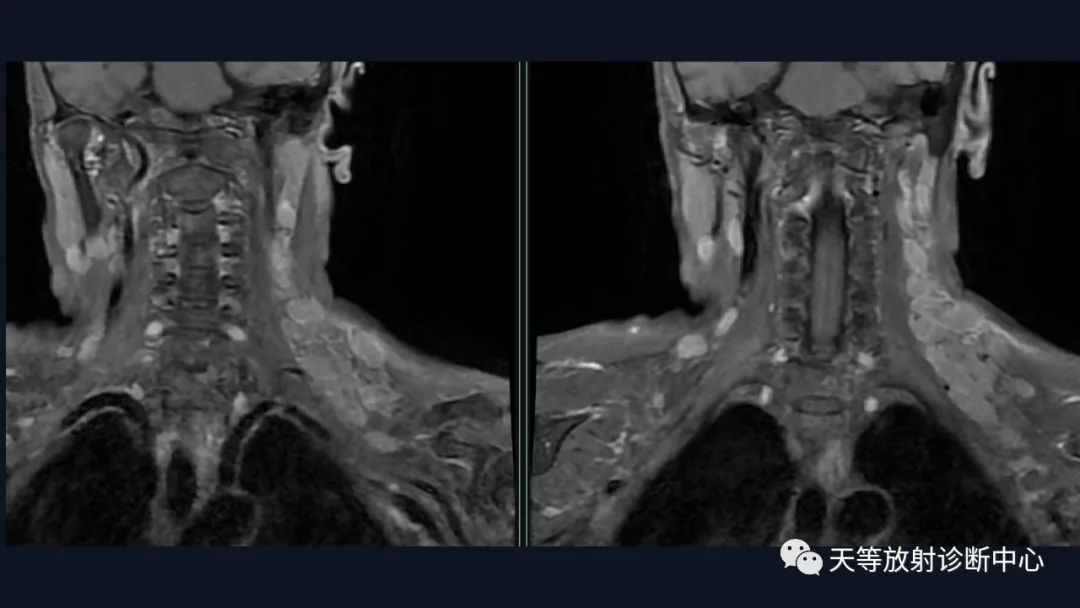

主 诉:发现左侧颈部隆起1周。

现病史:诉于2019年10月14日在无明显诱因下出现左侧颈部隆起,无疼痛,无咳嗽、咳痰,无发热、声嘶,无鼻塞、流涕,无鼻出血、抽吸性血痰,无耳鸣、耳漏,无头晕、头痛,无呼吸困难、吞咽困难等。病后曾自行服药及在当地输液治疗(具体不详),颈部隆起无变化,亦无红肿热痛表现。今日我院就诊,门诊医师遂拟”颈部肿物”收住入院。病后患者精神、睡眠、食欲欠佳,二便正常,体重无减轻。

结合颈部、胸廓入口区及腋窝多发淋巴结肿大并相互融合。

综合考虑淋巴瘤